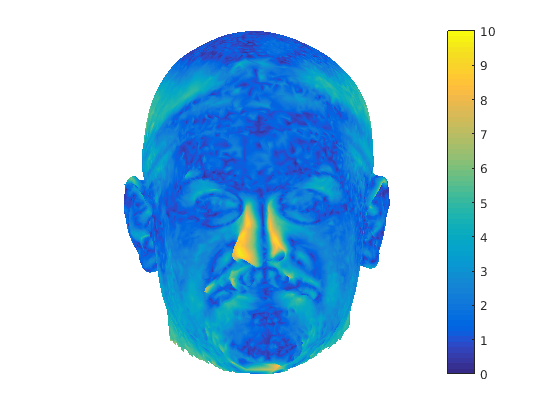

The region that the head scan and its reflection lie in is pre-partitioned into cuboid bins to reduce the computational cost of nearest neighbour search. Fig. 11 show the results of global symmetry plane alignment for 8 adult male samples from the headspace dataset. From observing 100 of these scans we have noticed that the nose, a cartilaginous structure, is often not aligned with the global symmetry plane and regions around the nose area are often rejected as outliers in the trimmed ICP process. As a result, it is not possible to build a good profile model of the face using global symmetry alone, as the ridge of the nose is often not sufficiently well aligned with the global symmetry plane. This motivated us to find the facial contour using local symmetry considerations.

In order to find the facial contour we implemented a piecewise ICP process across the glocal symmetry plane. Each head is first rotated such that its global symmetry plane is coincident with the Y-Z plane. The facial region, as defined by the sparse model fit is then divided into a set of horizontal strips (we use 20mm steps between the nasion and pognion) in the dimension, with the back of the head being cropped out. We apply our trimmed ICP algorithm to each separate strip, so that a local symmetry plane is found for each strip and the facial contour is found by intersecting this sequence of local symmetry planes with its corresponding facial strip. For each strip (index ), we use the strip below and the strip above in the trimmed ICP process in order to reduce the sensitivity of the local symmetry planes to noise. This process is only applied to the face and the cranial region is dealt with as a whole. This is because, in strips, it does not provide sufficient constraints for ICP to lock onto and the two surfaces can slide over each other freely. Fig. 12 shows facial local symmetry contours deviating from the global symmetry plane. Points on the head profile are then extracted by detecting mesh arcs that cross a symmetry plane and linearly interpolating to extract 3D vertices that lie on that symmetry plane.